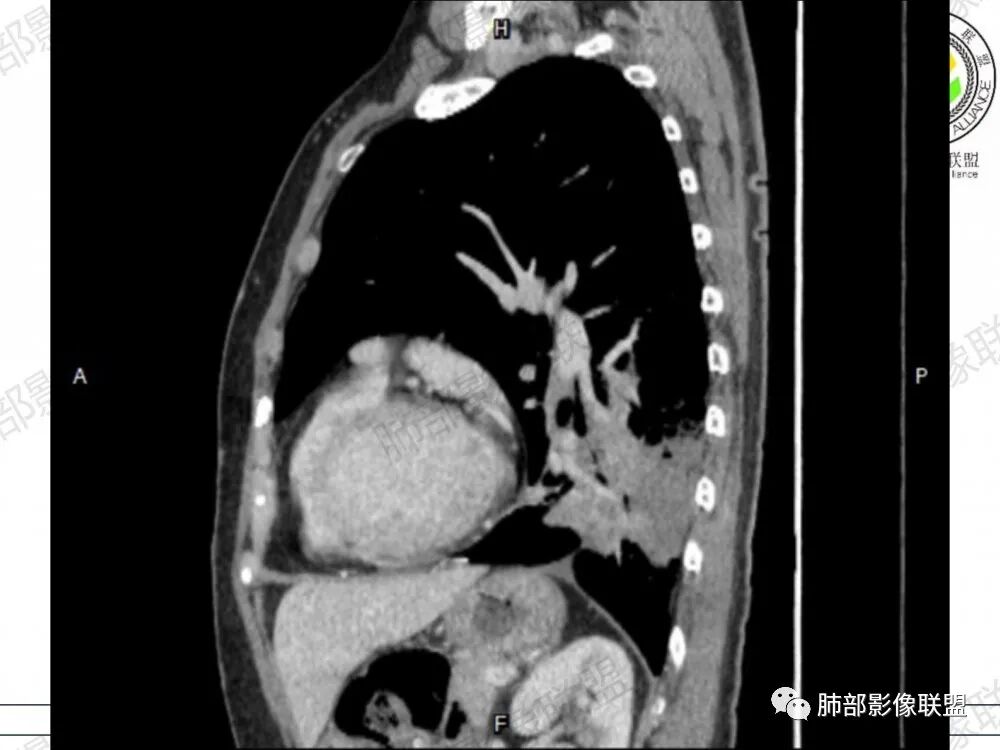

晨读病例,老年人男性 左肺下叶病灶,实性病变加上边界清晰的磨玻璃影,实性病变可见明显的膨胀性生长,增强实性部分可见血管照影征,考虑腺癌,粘液腺癌可能。

左肺下叶胸膜下混合磨玻璃影,磨玻璃边界清晰,支气管进入后堵塞,增强轻中度强化,无明显坏死空洞。

空腔+铺路石征+边界清楚GGO+病灶内血管局部扭曲+强化不均匀+病史长,指向腺癌,特别是粘液腺癌

晨读:左肺下叶胸膜下实性高密度影,部分伴有网格样增厚,内部可见小空泡,壁光滑,周围伴有磨玻璃影,边界清,近端可见支气管穿行,远端支气管堵塞,胸膜下脂肪间隙可见,病变整体收缩,部分有彭隆,增强后可见血管穿行,强化尚均匀。

左肺下叶实变及磨玻璃影,宽基底与胸膜相远,磨玻璃边界清晰,边缘膨隆,病变内近端支气管堵塞,不均匀强化,可见血管影,考虑腺癌,鉴别结核

胸CT:左下叶胸膜下大片斑片影,长轴沿胸膜分布,实变、GGO混杂,磨玻璃边界清晰,粘液密度,小叶内间隔增厚,支气管进入后堵塞(枯枝),增强轻中度强化,血管造影征。常规考虑:肺腺癌?淋巴瘤?鉴别不典型病原体感染。

周围GGO,呈碎石路征,边界清楚

主体病灶

应该是空洞

如果是支气管,说明局部有占位效应,将支气管推移

2、影像表现:无肺气肿背景,病变定位于左肺下叶背内侧基底段,病灶呈不规则团块影,靠近胸膜侧,其内密度不均匀,内见空洞、实变及磨玻璃影,磨玻璃影呈碎石路征,边界清楚,实性肿块边界膨隆,其内见空洞。空洞周围比较实。病灶较大的支气管通畅,细小的支气管成“枯枝征”。无胸膜增厚及胸膜腔积液,增强扫描呈中度强化,见血管造影征。